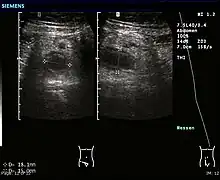

Ultrasound

Abdominal ultrasonography, preferably with doppler sonography, is useful to detect appendicitis, especially in children. Ultrasound can show the free fluid collection in the right iliac fossa, along with a visible appendix with increased blood flow when using color Doppler, and noncompressibility of the appendix, as it is essentially walled-off abscess. Other secondary sonographic signs of acute appendicitis include the presence of echogenic mesenteric fat surrounding the appendix and the acoustic shadowing of an appendicolith.[45] In some cases (approximately 5%),[46] ultrasonography of the iliac fossa does not reveal any abnormalities despite the presence of appendicitis. This false-negative finding is especially true of early appendicitis before the appendix has become significantly distended. Also, false-negative findings are more common in adults where larger amounts of fat and bowel gas make visualizing the appendix technically difficult. Despite these limitations, sonographic imaging with experienced hands can often distinguish between appendicitis and other diseases with similar symptoms. Some of these conditions include inflammation of lymph nodes near the appendix or pain originating from other pelvic organs such as the ovaries or Fallopian tubes. Ultrasounds may be either done by the radiology department or by the emergency physician.[47]